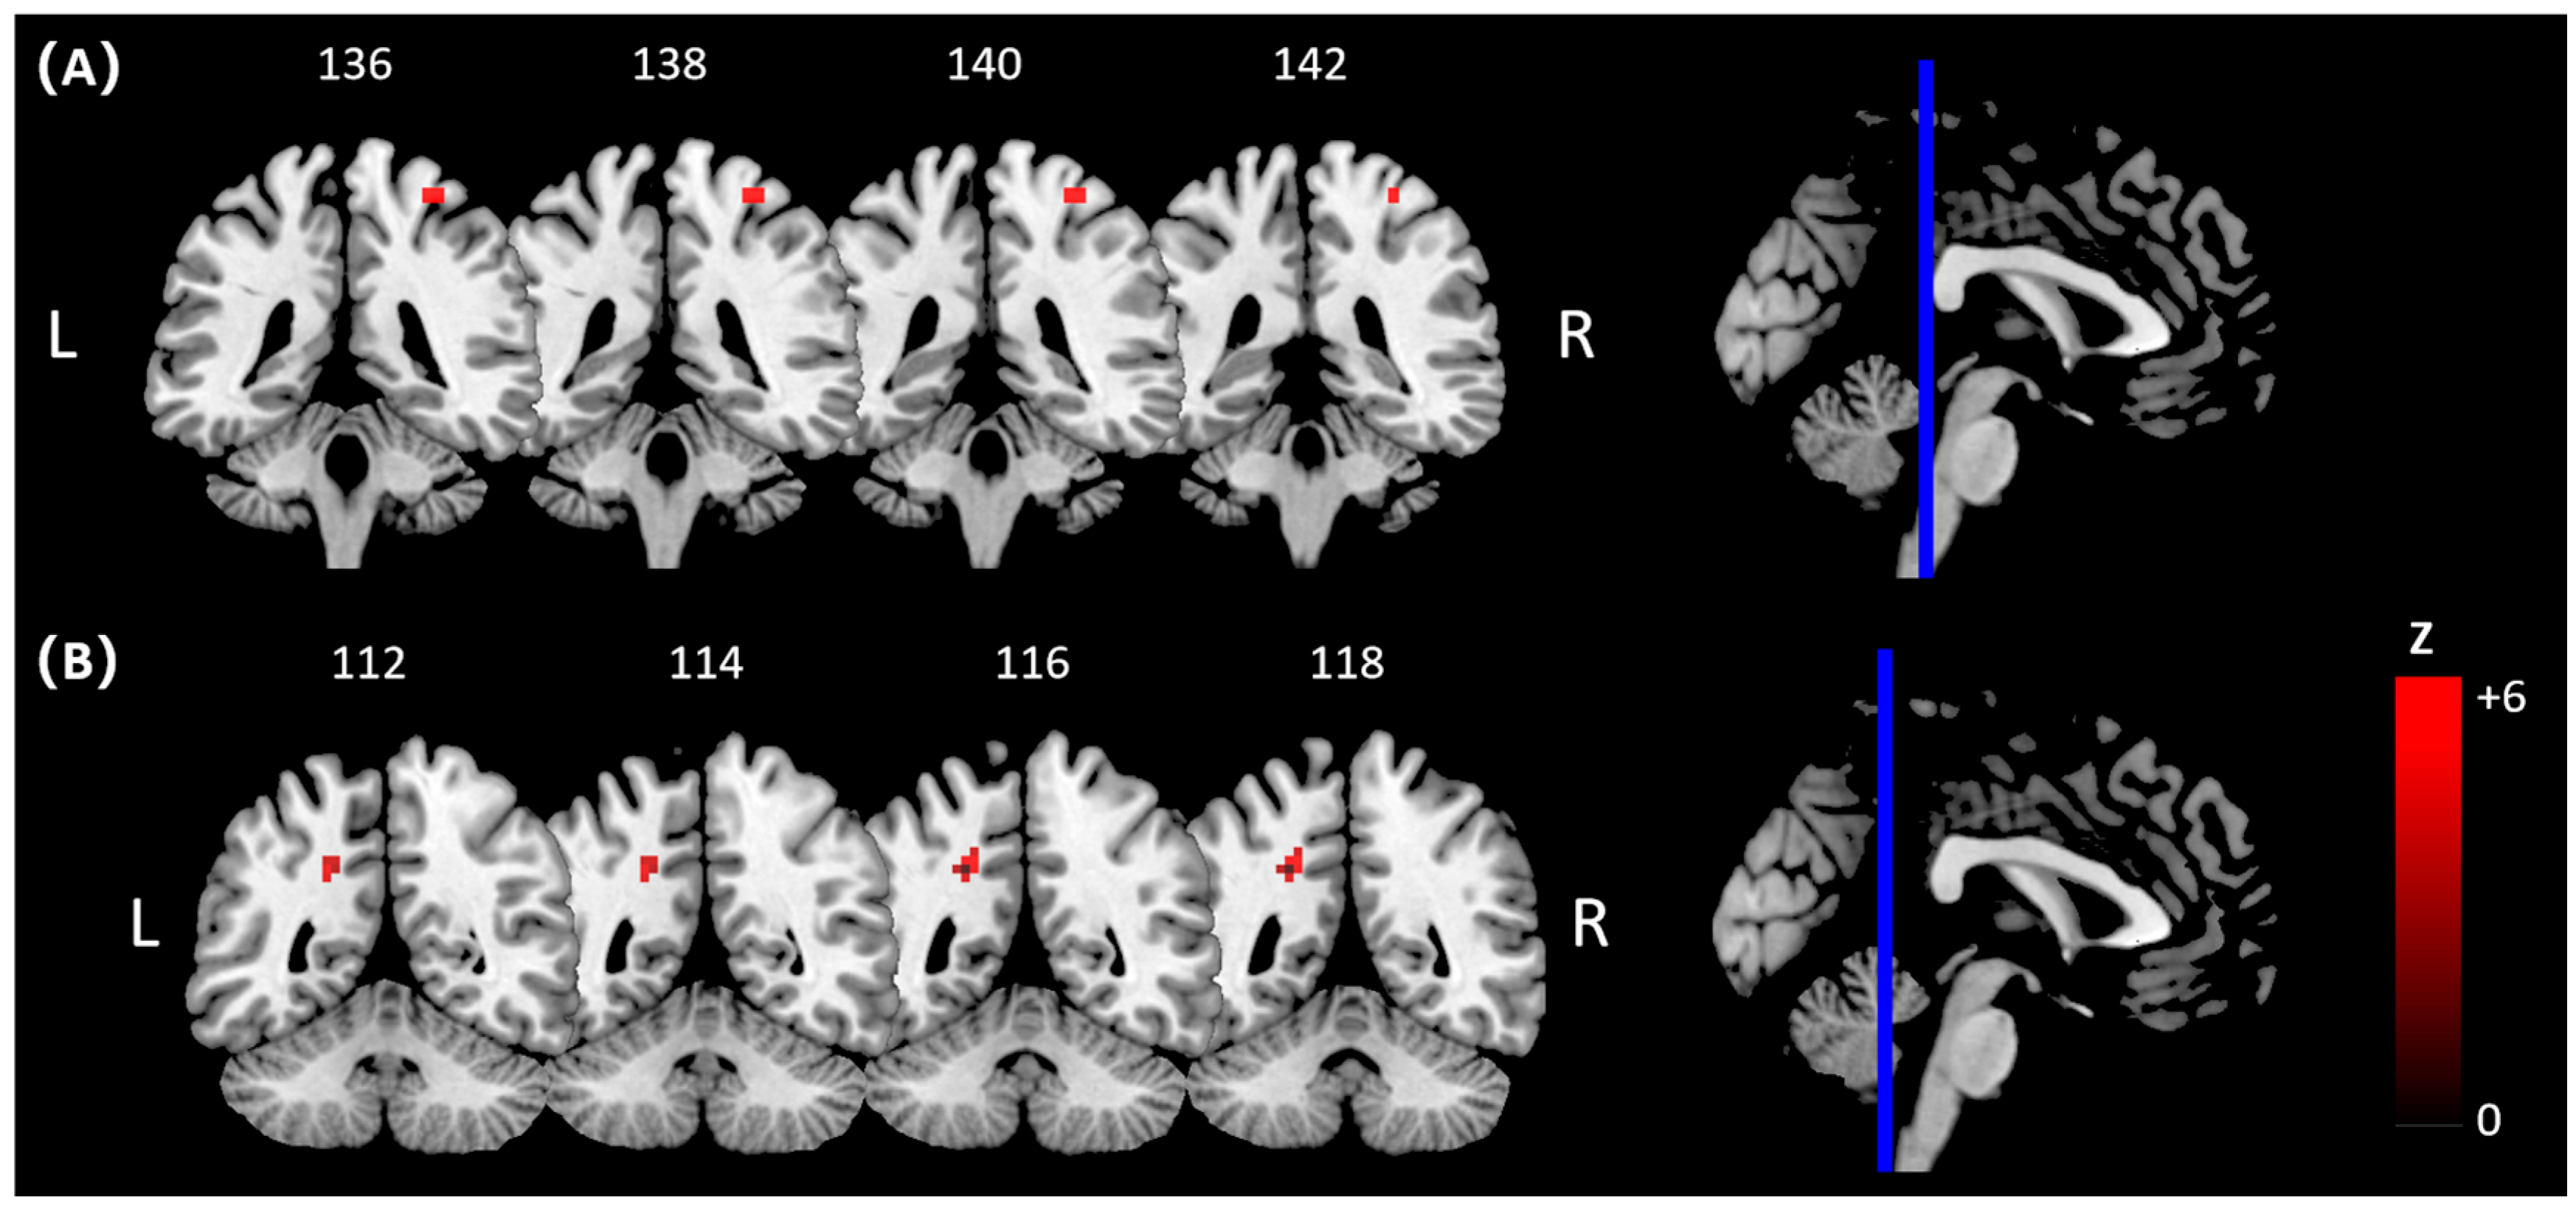

| Comparisons | Brain Regions/BA | Peak MNI Coordinates | Cluster Voxels | Peak Z Values | |||

|---|---|---|---|---|---|---|---|

| x | y | z | |||||

| Pre-hitting | Golf group > Control group | R Insula/BA 48 | 39 | 15 | 0 | 67 | 3.90 a |

| R Posterior Cingulate Cortex (PCC)/BA 17 | 18 | −60 | 12 | 69 | 3.85 a | ||

| Hitting | Golf group > Control group | R Cerebelum/BA 19 | 18 | −57 | −27 | 99 | 4.36 a |

| L Postcentral Gyrus/BA 2 | −36 | −39 | 57 | 105 | 4.26 a | ||

| R Postcentral Gyrus/BA 2 | 27 | −39 | 66 | 255 | 4.04 a | ||

| Golf group < Control group | R Cerebellum/BA 18 | 12 | −72 | −15 | 114 | 4.05 a | |

| Hitting > Pre-hitting | Golf group < Control group | L Postcentral Gyrus/BA 2 | −36 | −39 | 57 | 175 | 4.54 a |

| R Postcentral Gyrus/BA 4 | 33 | −33 | 66 | 199 | 4.06 a | ||